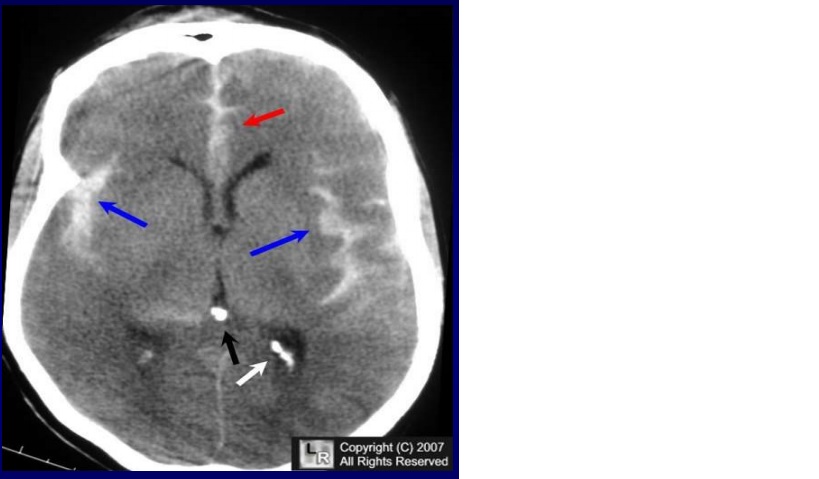

Ruptured right middle cerebral artery aneurysm requiring clipping, and subsequent cerebral vasospasm and delayed cerebral ischemia, A, Noncontrast head CT shows a large intraparenchymal component (thick arrows), small subarachnoid hemorrhage (arrowheads), and intraventricular hemorrhage with hydrocephalus (thin arrows). B, Cerebral angiogram reveals a right middle cerebral artery aneurysm (yellow arrow) as the culprit of the hemorrhage. C, Three-dimensional cerebral angiogram shows the complicated anatomy of this middle cerebral artery aneurysm with multiple vessels coming off the aneurysm and areas of irregular outpouching (blue arrows).

Nhận xét: Trường hợp này cho thấy bệnh nhân có chỉ định phẫu thuật (surgical clipping ) do vị trí nông của phình động mạch ở phần xa động mạch não giữa và giải phẫu của phình động mạch với nhiều mạch thoát ra khỏi phình mạch. Nó cũng cho thấy bệnh nhân có máu tụ lớn ở thái dương (có hoặc không có xuất huyết dưới nhện), phải có chẩn đoán hình ảnh mạch máu, vì phình động mạch não giữa có thể là thủ phạm.